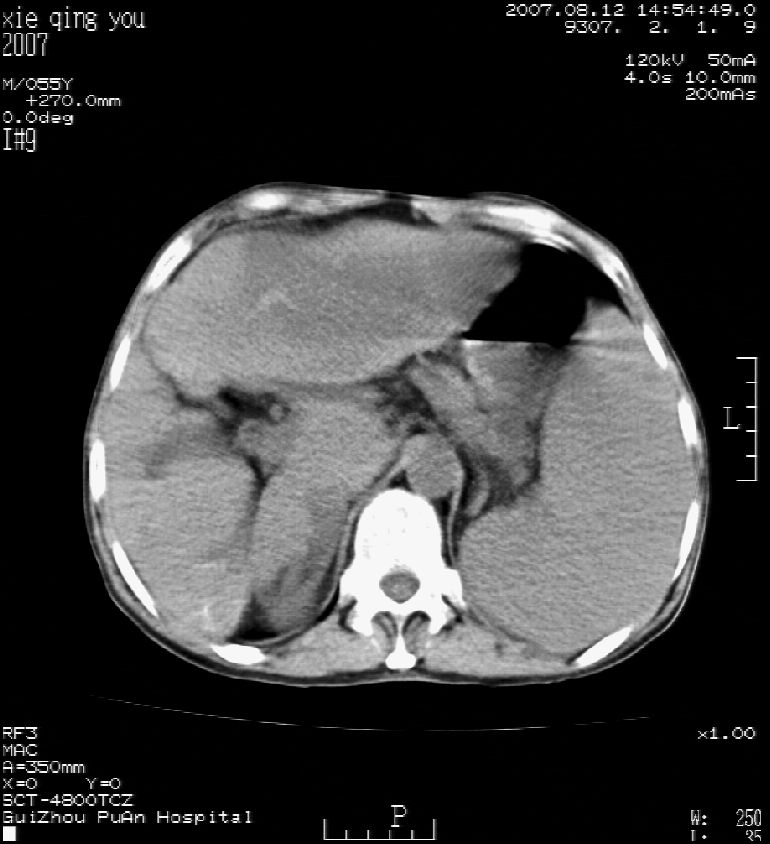

男 55岁  反复上腹痛1年,伴恶心呕吐。2005年做第一次检查后,到外院做b超检查提示肝囊肿,未做任何手术。2006年做过胆总管结石术。骨窗未见异常

2007年8月片

这个病灶很有意思,怎么可能没有了呢?我考虑当时很可能是肝脏脓肿(b超示囊肿是有可能误诊的,因为影像表现都是低回声吗?),现在脓肿吸收了,肝脏萎缩,肝裂增宽了.别的肝叶代偿增大,不过现在左内叶的确有个占位,肝内多发结石,脾脏比以前大,不排除有肝硬化可能.建议增强扫描给于定性!!!!

肝硬化\\脾大,肝左叶肝癌可能性大,建议增强扫描.肝内胆管多发性结石.

1, 肝硬化,脾大;2,肝左叶肝癌可能性大,建议增强扫描.3,肝内胆管多发性结石.

至于肝右叶病灶为什么消失只有结合治疗史综合考虑。

考虑肝内胆管多发结石引起的肝内局部炎症,这样可以解释2005年肝右叶病灶的吸收和左叶新病灶.

肝硬化、脾大、肝内胆管多发结石。肝左叶低密度占位。建议增强扫描.排除肝癌